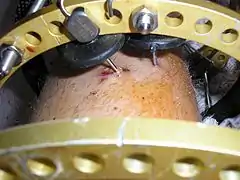

The photographs and radiographs illustrate the application and emplacement of an external fixator, an Ilizarov apparatus, to repair the open fracture of the lower left leg of a man. The photographs were taken four weeks after the patient fractured the shinbone (tibia) and the calfbone (fibula) of his left leg, and two weeks after the surgical emplacement of the Ilizarov apparatus to immobilise the leg and isolate the wound and fracture site to facilitate healing.

X-ray of the open fracture site immediately after installation of the Ilizarov apparatus. Superior perspective of the Ilizarov apparatus and the Kirschner pins in the left leg at two weeks post-surgical.

Superior perspective of the Ilizarov apparatus and the Kirschner pins in the left leg at two weeks post-surgical.

Superior perspective of the apparatus emplaced into the left leg of the patient.

Superior perspective of the apparatus emplaced into the left leg of the patient. X-ray of the fracture site and the emplaced apparatus, two months post-fracture; perspective 1-4.